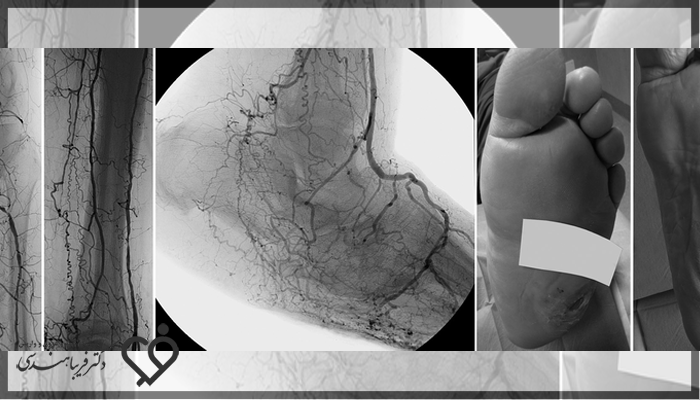

آنژیوگرافی پای دیابتی یکی از روشهای حیاتی و دقیق برای تشخیص و درمان مشکلات عروقی در بیماران دیابتی است. اگر شما یا یکی از نزدیکانتان به دیابت مبتلا هستید، احتمال بروز مشکلات گردش خون در پاها میتواند زندگی روزمره را به شدت تحت تاثیر قرار دهد و حتی خطراتی مانند زخمهای مزمن یا قطع عضو را به همراه داشته باشد. اینجاست که آنژیوگرافی به عنوان یک ابزار کلیدی وارد عمل میشود؛ روشی که به پزشکان امکان میدهد تا رگهای مسدود یا تنگ شده را بهدرستی شناسایی کنند و با درمان به موقع، از بروز عوارض جدی جلوگیری کنند. در این مقاله با شما همراهیم تا با این تکنیک مهم آشنا شوید، نگرانیهایتان را کاهش دهید و امید به درمان بهتر را بیشتر کنید.

آنژیوگرافی برای پای فرد دیابتی زمانی لازم است که فرد بیمار علائمی مثل بیحسی، درد، ضرب و یا گزگز را در قسمت پا و ساق پا احساس کند. در چنین شرایطی فرد بیمار باید به پزشک معالج خود مراجعه کرده تا پزشک بتواند به بررسی دقیق مشکلات بیمار بپردازد و زمانی که پزشک به عفونتهای زیاد و یا قطع عضو مشکوک شود، از آنژیوگرافی به منظور شناسایی دقیقتر استفاده خواهد کرد.

عکس و فیلم آنژیوگرافی این امکان را به پزشکها میدهد که به صورت کامل از شدت آسیبها آگاه شده و آنها را مورد بررسی قرار داده تا بتوانند اقدامات درمانی را به منظور جلوگیری کردن از عفونت بیشتر و همچنین قطع عضو انجام بدهند.

آنژیوگرافی پای افراد دیابتی این امکان را به پزشکها میدهد تا میزان مشکلات عروقی و همچنین انسداد رگها در پاهای فرد بیمار را به صورت کامل و دقیق شناسایی کند.

در طول مدت زمان آنژیوگرافی، پزشکها تصاویر زندهای را از وضعیت کنونی عروق و جریان خون بیمار دریافت میکنند و در صورتی که نیاز باشد اقدامهای درمانی را به سرعت انجام میدهند.